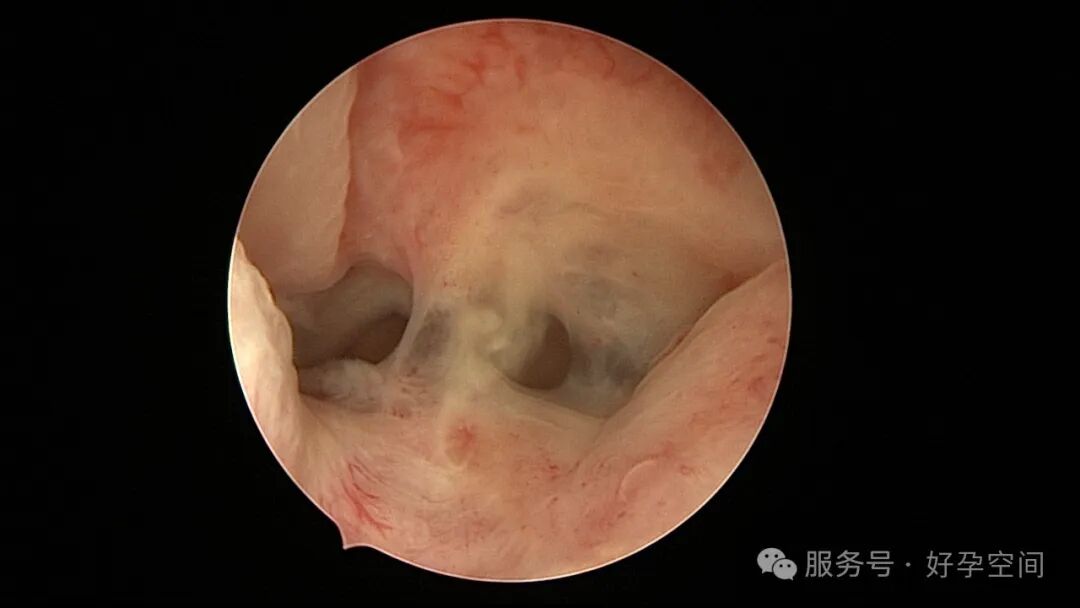

试管前宫腔镜检查